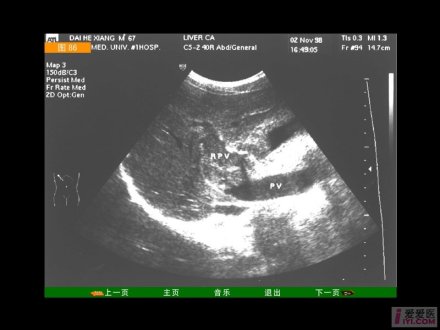

根据解剖关系考虑病变的脏器:右季肋部是肝、胆、十二指肠、结肠肝曲、右肾和右膈所在区域。因此右季肋部痛首先要考虑这些脏器的病变。此外,右季肋部受肋间神经支配,右胸部病变刺激肋间神经时,也可引起右季肋部痛。